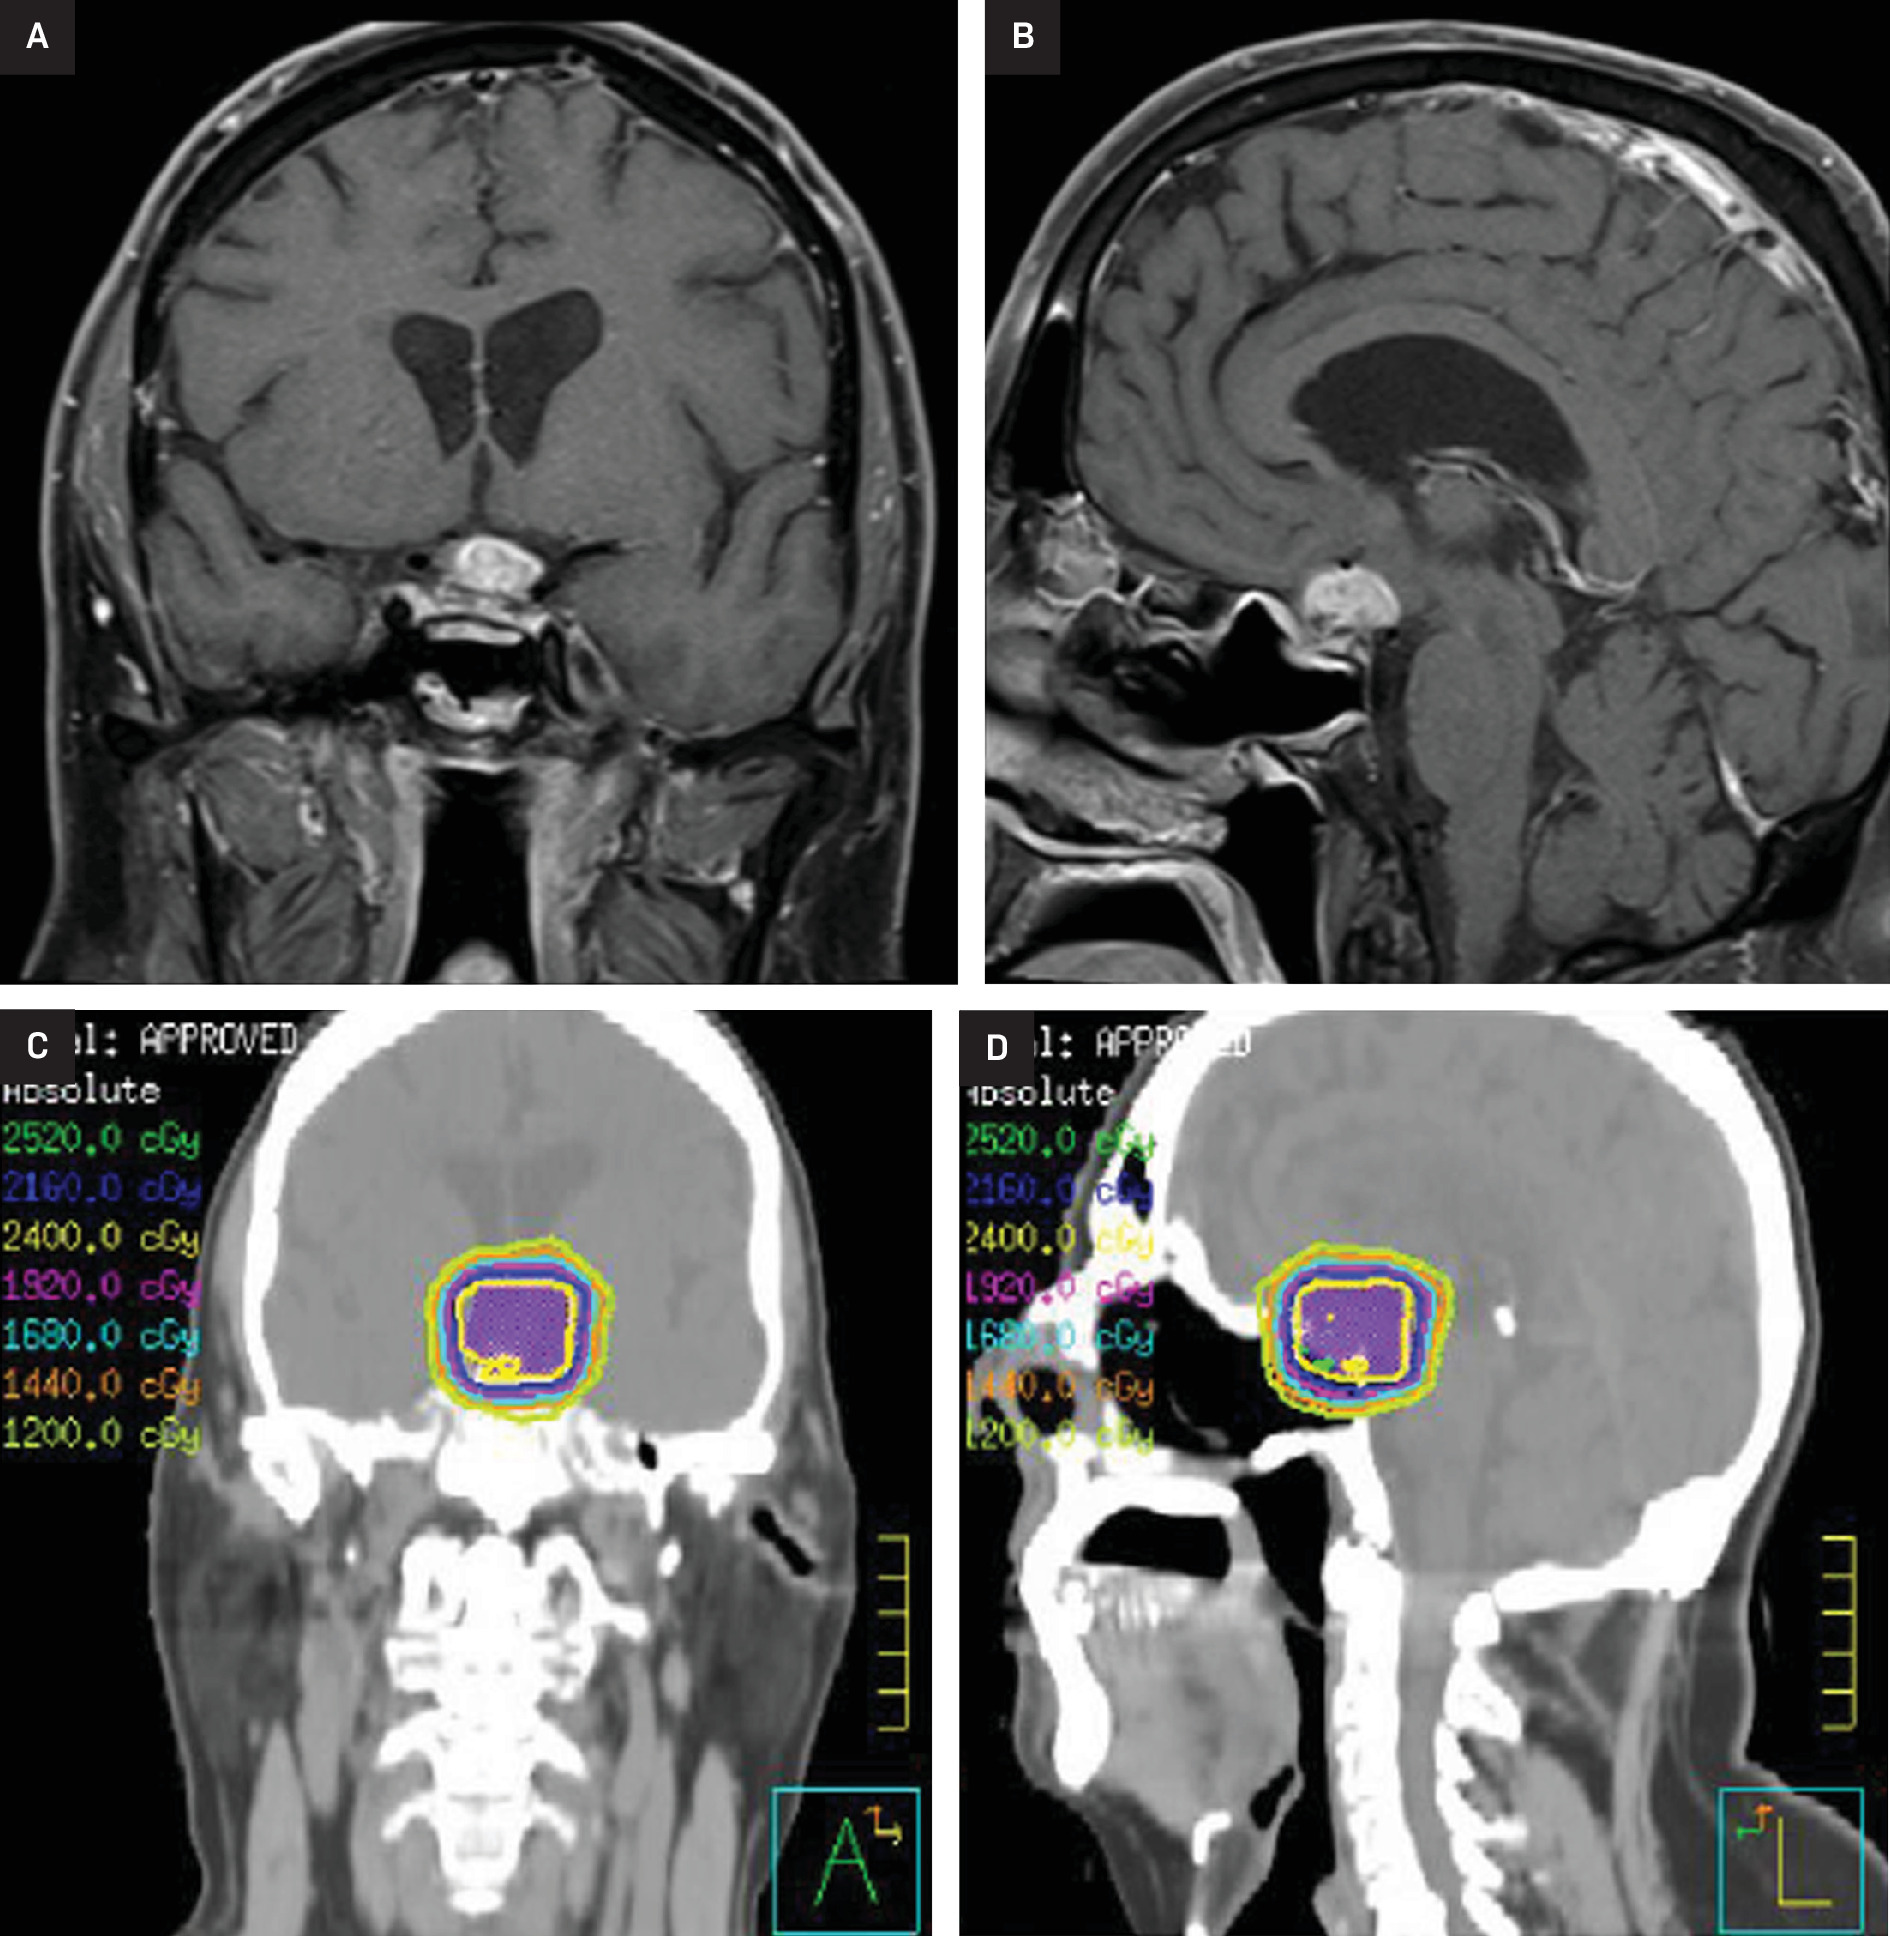

After 2 years of stability, imaging revealed further progression with mass-like enhancement involving the suprasellar cistern, optic apparatus, and hypothalamus, associated with worsening vision. The patient’s case was discussed at multidisciplinary tumor board with the recommendation for radiation. He then received 24 Gy in 12 fractions with 6 MV photons utilizing 2 non-coplanar VMAT arcs and cone-beam CT for image guidance (Figure 1). Areas of progression and enhancement were targeted, including the sella, optic nerves and chiasm, and hypothalamus. He experienced no immediate side effects except for mild fatigue. Within 6 months of his initial course of RT, his vision had improved. At 3 years post RT, he had stable vision with very slight progression on imaging and remained on low-dose steroids. However, by 6 years after RT, the patient’s suprasellar lesion had notably enlarged with an increased mass effect on the optic chiasm as well as corresponding declines in his vision (light perception only in the left eye; worsening right-sided peripheral vision).